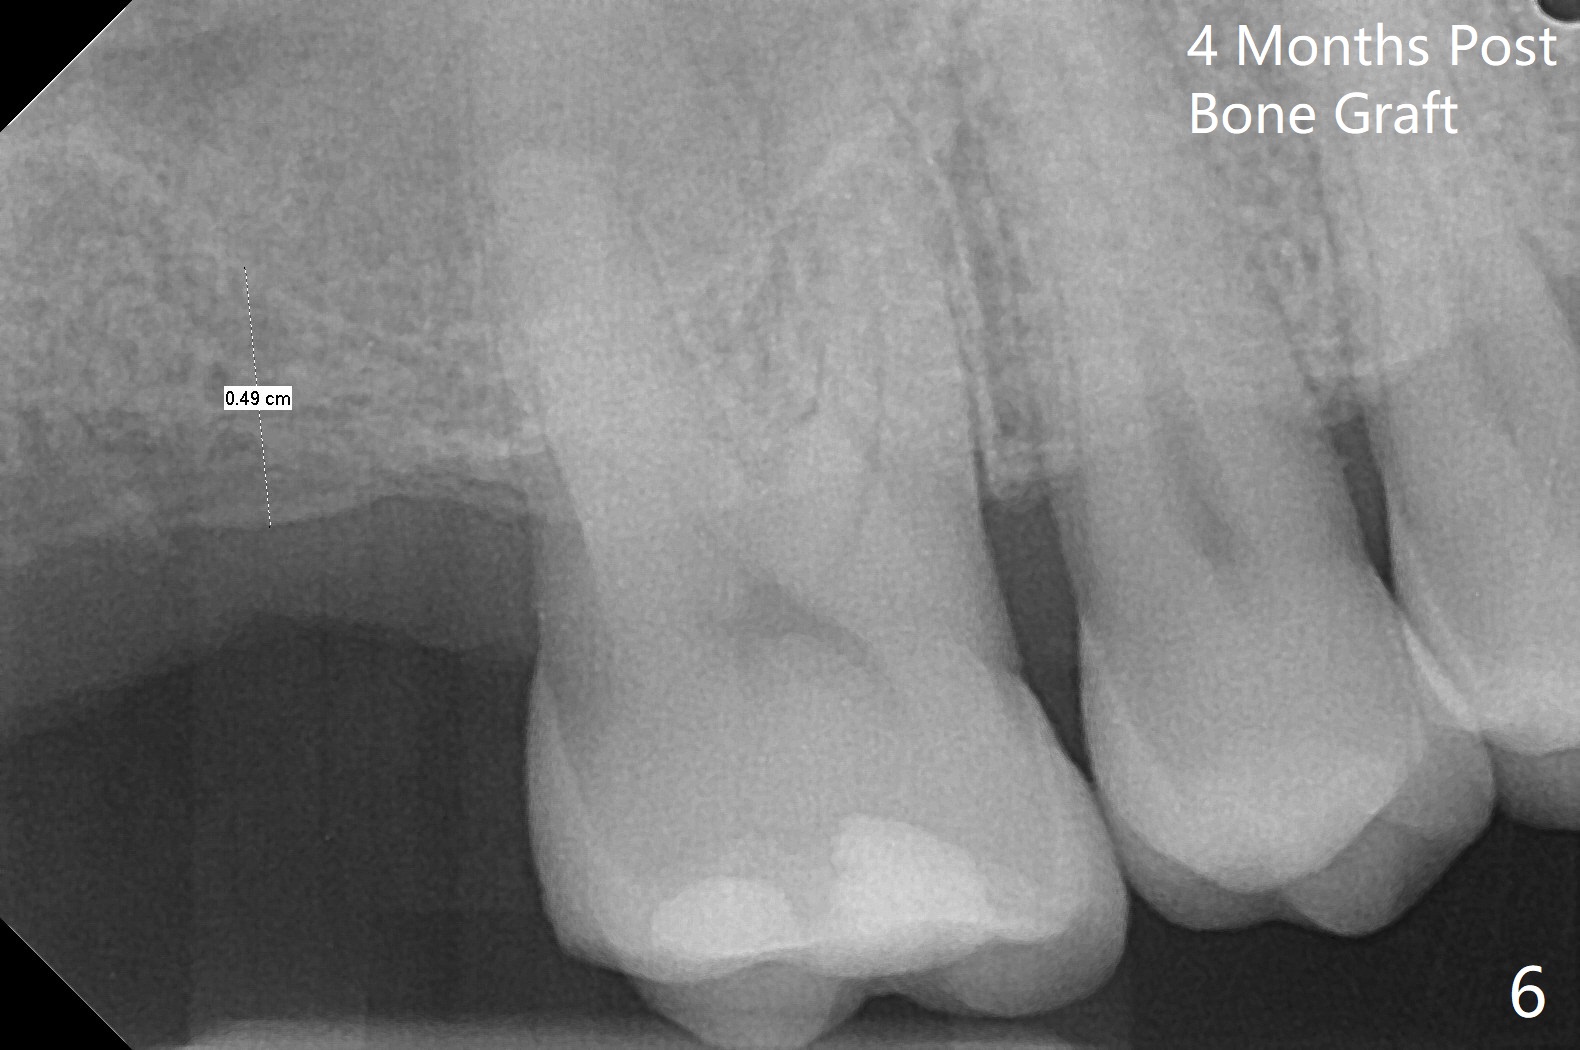

在导航协助下,我们可以一期准确进行上颌窦提升,即刻种植,即刻修复。56岁男(吸烟)右侧上颌窦有粘液囊肿,右上七牙齿折裂(图一(术前):^),CT检查表明植体植入腭侧牙槽窝比较合适(图一:>)。为了减少对囊肿损伤,我们使用导板(图二 *)完成初步钻洞,接近上颌窦底板,然后放置粘性骨(>),用4x10毫米dummy(报废)植体慢速(15 RPM)旋入进行内提升,同时准确控制深度。再次放置骨粉,使用4.5x10毫米报废植体上推;最后放置骨粉后(图三 >),植入正式植体(5x9毫米,扭力大于35Ncm)和修复基台(6.5x4(4)),怀疑后者没有完全就位,后来使用小的基台(图四,并且调整高度),植体和基台周围放置骨粉(*),然后安置临时牙冠。咬颌面没有接触,临时牙冠主要目的是防止骨粉丢失。反复告诉病人不能咬东西。术后两周病人主诉临时牙冠太大,试图减少颊舌侧向,不幸的是却减少近中远中向,造成临时牙冠不稳定。一周后牙冠和基台松动,取出,放置愈合螺帽,牙槽窝基本愈合。病人将术后近四个月复诊,拍摄根尖片和咬翼片,如果骨质愈合良好,尝试在尚未完全愈合的伤口放置小号愈合基台。术后5个月牙冠粘固后拧紧植体松动,取出(图五(*:缺损)),植骨。四个月后骨质高度近5毫米(图六)。再次植入尽量避免窦膜穿孔(粘液囊肿),塞入PRF膜。Return to Upper Molar Immediate Implant, Prevent Molar Periimplantitis (Protocols, Table) No Deviation 不理想病例 开场白Xin Wei, DDS, PhD, MS 1st edition 08/10/2020, last revision 06/12/2021